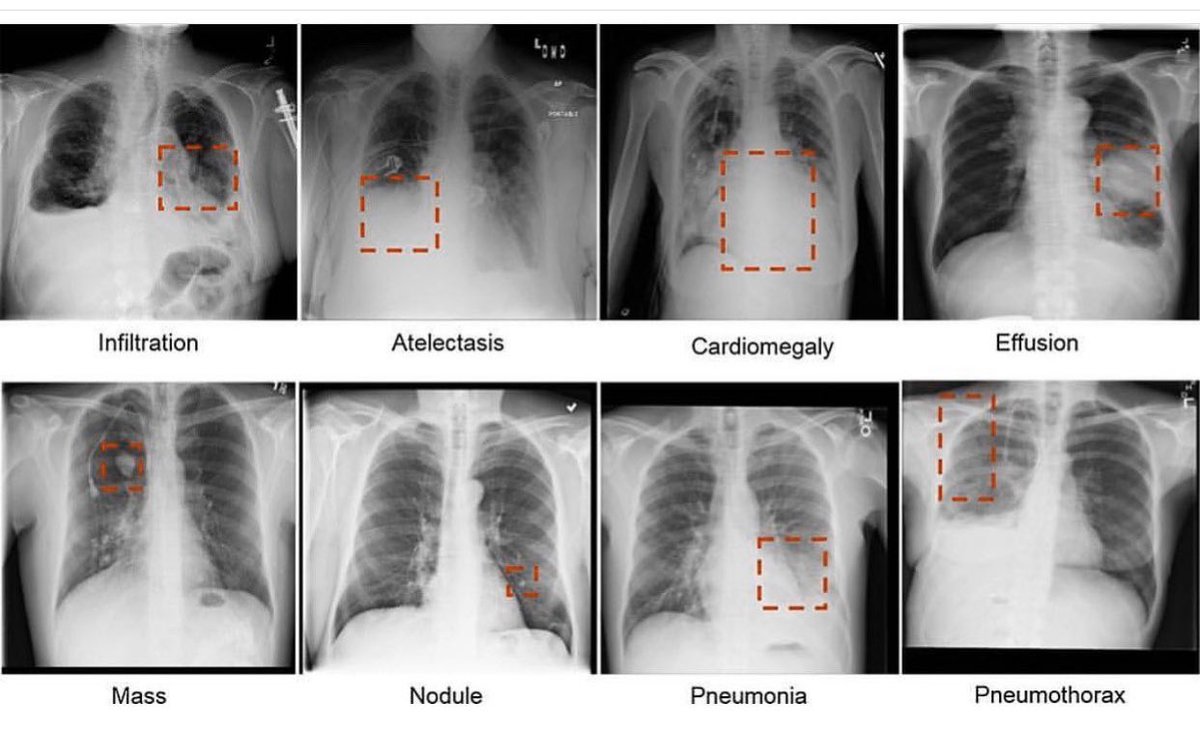

Что можно увидеть с помощью рентгена?

Рентгенография используется не только при хронических заболеваниях, но и при подозрении на развитие опухолевых образований, при травмах, острых абсцессах, переломах костей. Это быстрый и точный метод, предоставляющий точную картину происходящего в настоящий момент.

При переломах между светлыми участками костей видны темные разрывы.

Камни в почках, желчном пузыре выглядят как отдельные белесые участки.

При введении контрастного вещества опухолевые образования на снимках остаются “незаполненными” и отличаются по цвету от структур органа.

При обследовании сердечно-сосудистой системы на проблемных участках видны темные разрывы.